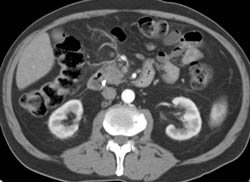

Diagnosis

Intraductal Papillary Mucinous Neoplasm (IPMN)